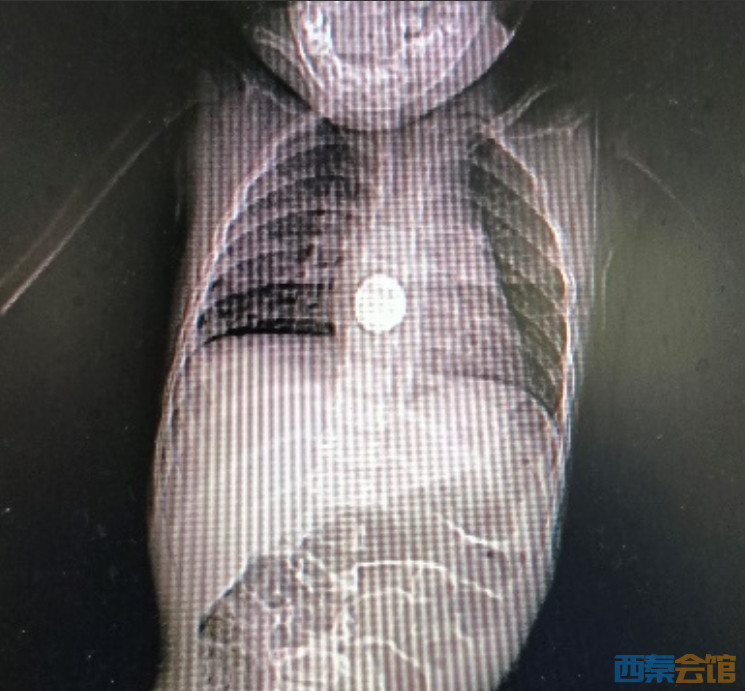

近日,一名1岁11个月的患儿因发热、咳嗽、呕吐3天,胸部摄片发现食管金属异物存留,被紧急送入普洱市人民医院救治。

CT影像

患儿入院后进一步检查显示,食管(T5-6水平)有金属密度影,同时肺部存在炎性阴影。确定异物的准确位置后,在麻醉科与消化内科的共同协作下,医生用异物钳将其取出。